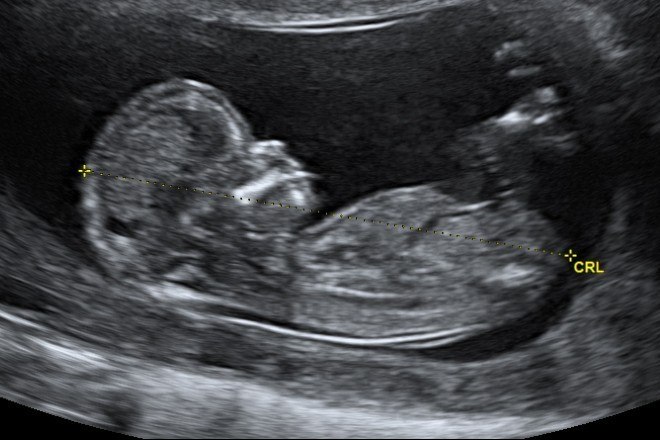

Tudo porque a jovem não se deu conta de que o reflexo sobre a bolsa deixou o acessório com a aparência de um exame de ultrassom

"Algumas pessoas realmente pensaram que eu estava anunciando minha gravidez", explicou Siophan ao tabloide Mirror, "o que me fez rir por ter colocado a legenda 'vamos nos embebedar'"

Mais tarde, a jovem decidiu deletar a imagem: "Ficavam me perguntando se eu achava sensato beber enquanto segurava um exame de ultrassom"

O registro foi feito no ano passado, no entanto, Siophan decidiu republicá-lo recentemente com outra legenda: "Um ano desde que todos pensaram que eu estava segurando um ultrassom de bebê"